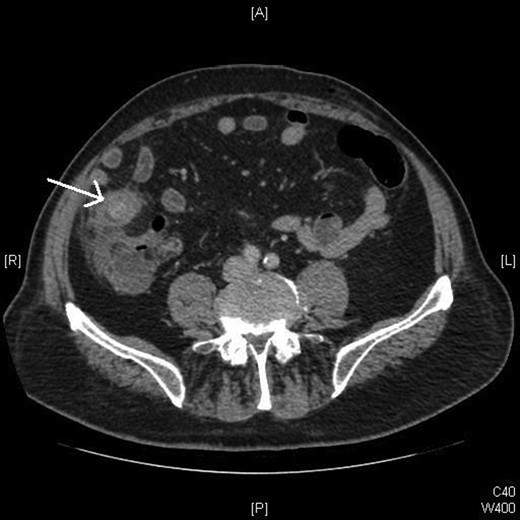

A computed tomography (CT) scan was performed in light of the patient's age (Fig. 1), which reported ‘a dilated fluid filled appendix, containing an appendicolith.’ Laparoscopic appendicectomy was therefore planned (Fig. 1).